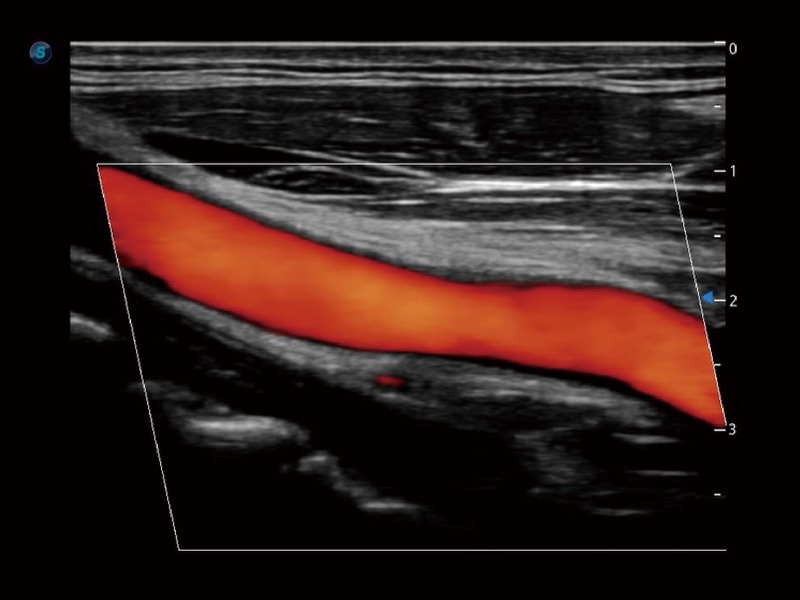

高分辨率血流成像技术提高了对低速血流信号的检测能力。在提高空间分辨率的同时,也克服了血流外溢现象,为用户提供更加真实的血流动力学信息。

血管内中膜的厚度值是预测心血管疾病风险的重要指标,Auto IMT可以实现血管近场和远场内中膜厚度的自动测量,为临床提供快捷有效的诊断工具。